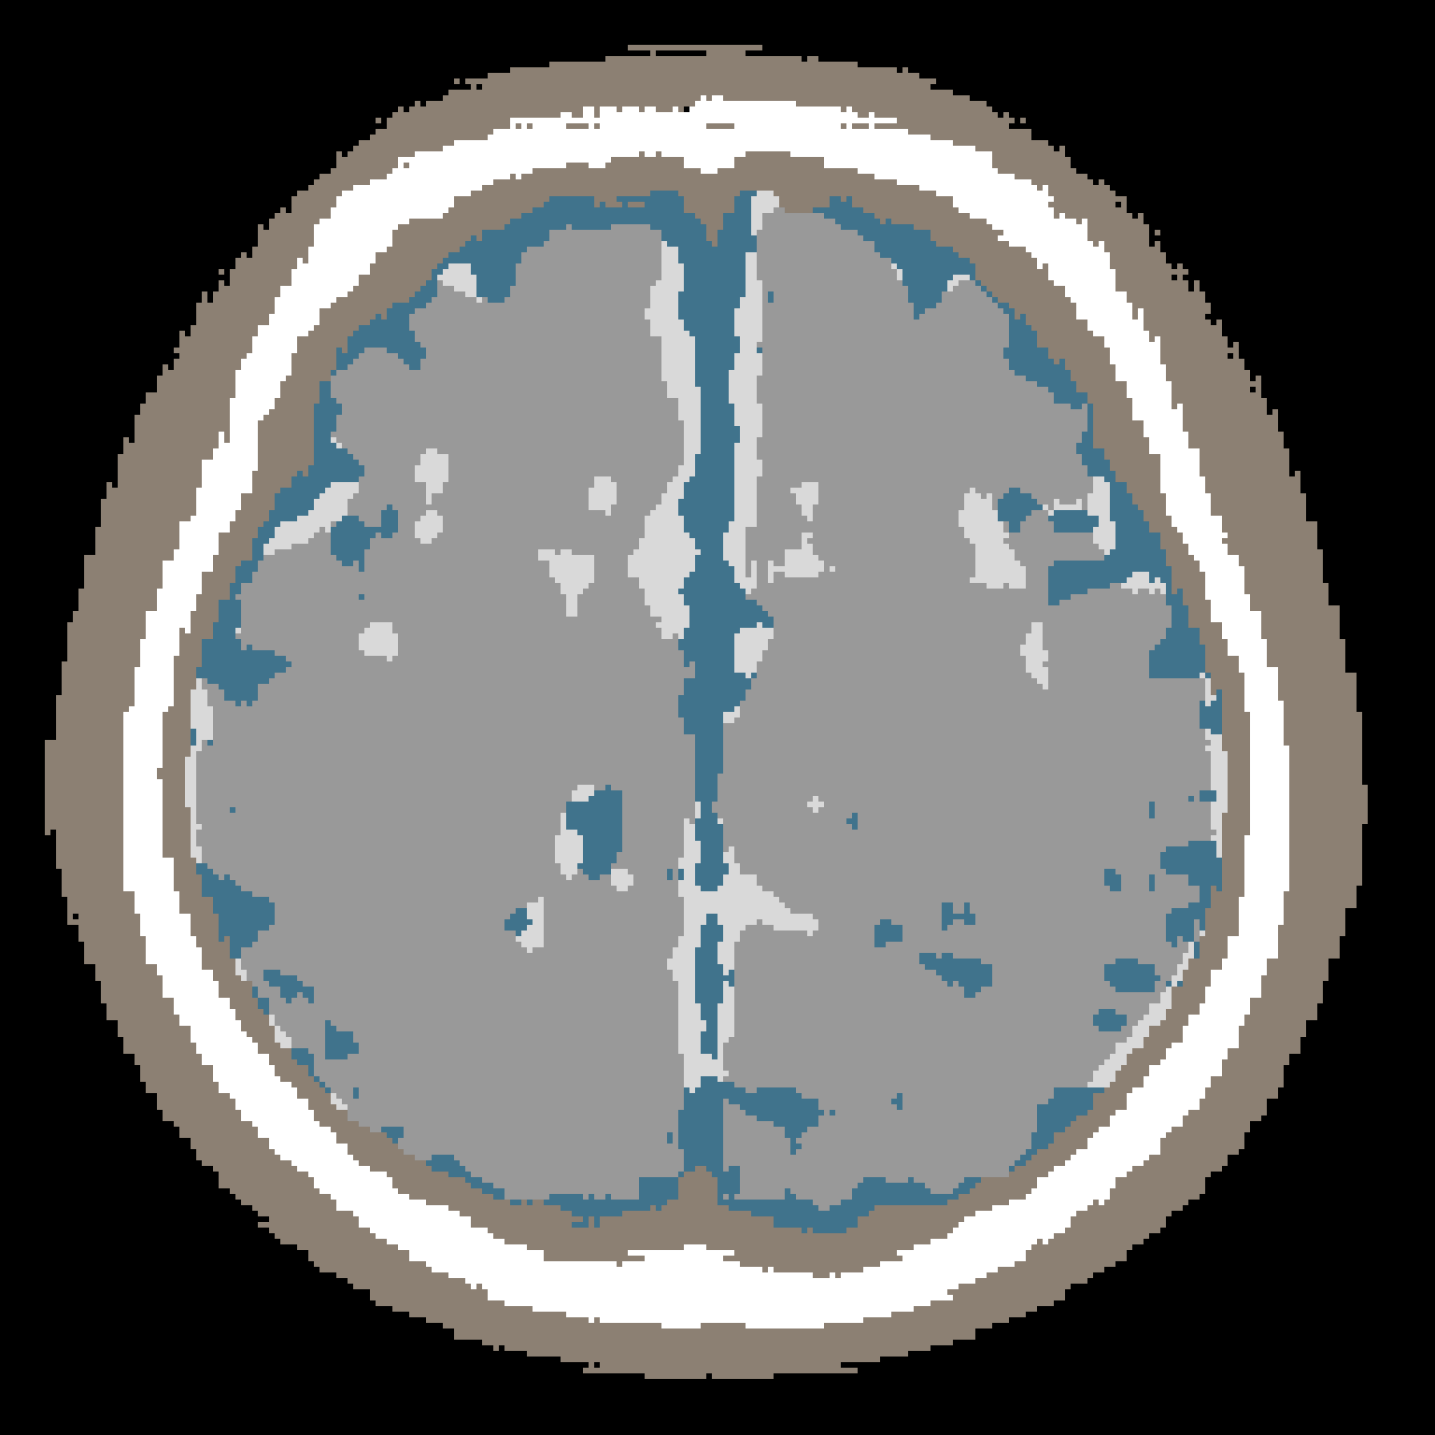

Figure 4 shows representative examples of real and synthetic brain segmentation masks generated by the proposed framework. The top row corresponds to samples generated without lesion conditioning (y=0y=0), while the bottom row shows samples generated with lesion conditioning (y=1y=1). - Across both settings, synthetic masks preserve global brain anatomy, clear tissue boundaries, and consistent class semantics comparable to real data. When lesion conditioning is enabled, ischemic infarct regions are generated without disrupting the overall anatomical structure.

Top row: Real masks

Bottom row: Synthetic masks

Figure 4: Qualitative comparison between real (top row) and synthetic (bottom row) brain segmentation masks generated without lesion conditioning (y=0y=0, left) and with lesion conditioning (y=1y=1, right).